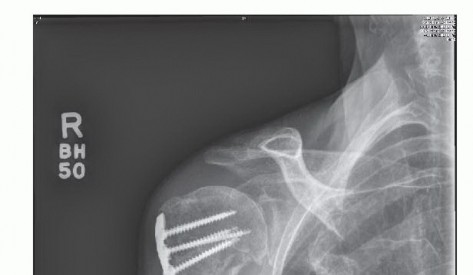

IMAGING AND OTHER DIAGNOSTIC STUDIES

Routine radiographic evaluation should include an anteroposterior (AP) view of the shoulder in neutral, internal, and external rotation as well as scapular Y and axillary lateral views.

Disuse osteopenia is often noted.

Concomitant findings may include calcific tendinitis or hardware signifying a previous surgical procedure (eg, open reduction and internal fixation, Putti-Platt) (

FIG 2

).

Magnetic resonance imaging (MRI) is obtained only if a rotator cuff tear or other soft tissue derangement is suspected.

We do not typically order an arthrogram or laboratory studies to confirm the diagnosis of adhesive capsulitis.

FIG 2 • Hardware on radiographs can be helpful in guiding treatment. In this instance, after treatment of a proximal humerus fracture with open reduction internal fixation, adhesions would be expected in the subdeltoid space.